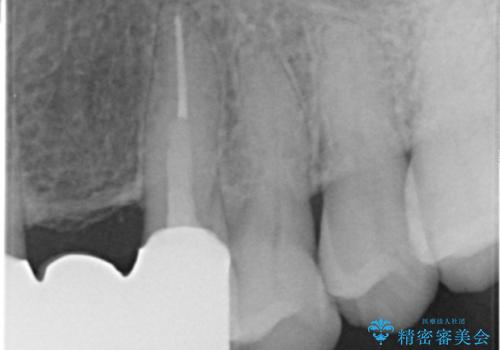

被せ物を除去したところ根管治療後の処置が不十分であったため、ファイバーコア(金属を用いない強くてしなやか材質の土台)を植立したのち、ジルコニアセラミッククラウンによる治療を行いました。

- ¥760,000 (仮歯¥10,000×6本、ファイバーコア¥20,000×5本、ジルコニアクラウン¥100,000×6本)費用は治療当時の料金となります